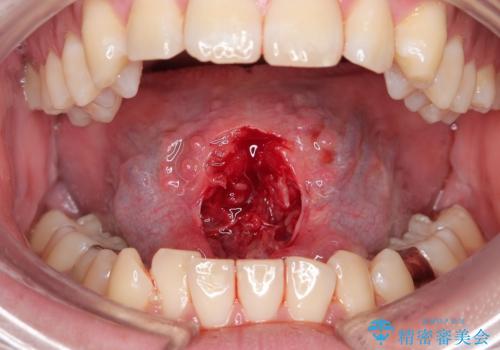

- 舌が動かしにくいと来院。

局所麻酔をし、舌小帯切除術を行うことになりました。

舌の可動範囲が広がり、満足していただけました。

舌小帯切除術は当日行うことができます。